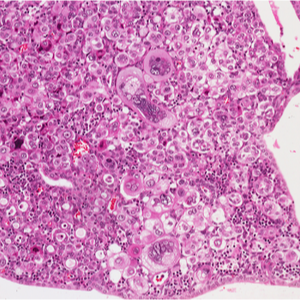

Kā attīstās vēža šūnas?